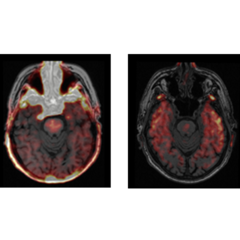

PET/MR brain scans in a person with Parkinson’s disease, using the tracer [11C]PK11195 as a marker of neuroinflammation (left image), and [18F]AV1451 as a marker of tau accumulation (right image)